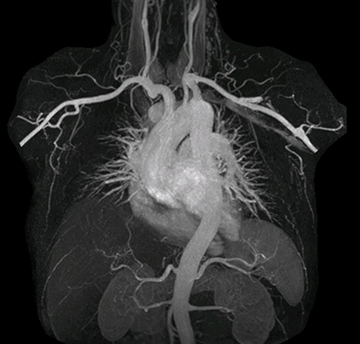

The subtractionless peripheral MR angiography shows improved vessel-to-background contrast and high resolution. Ingenia Ambition 1.5T.

“In MRA, the capacity to acquire a sequence in a single breathhold provides images that are motion-free and high in contrast and detail, advantages that aid in diagnosis,” he says. “With Compressed SENSE, we can reduce the time for the single breath-hold to just 2-3 seconds. Before Ingenia Ambition and Compressed SENSE, the breath-hold requirement was about 8 to 9 seconds, which was too long for some patients.”

“In our peripheral MRA run-off studies with Ambition we realize key benefits, including outstanding image quality and significantly reduced breath-hold and scan times, which not only benefit the patient, but also provide the opportunity to add sequences that could aid in diagnosis,” Dr. Peña says.

“Before we had Ingenia Ambition, our CE-MRA run-off studies would first acquire a dynamic pre-contrast scan with 20-25-second breath-holds, then inject the contrast, do another acquisition and then subtract the two,” says Avila. “Now, mDIXON XD allows us to complete the study in just one single pass – without need for a pre-exam – which eliminates subtraction artifacts and almost halves the scan time. In addition, mDIXON provides much better background suppression, which really improves vesselto-background contrast. And, thanks to Compressed SENSE, the single breath-hold is not long and we improve image resolution.”